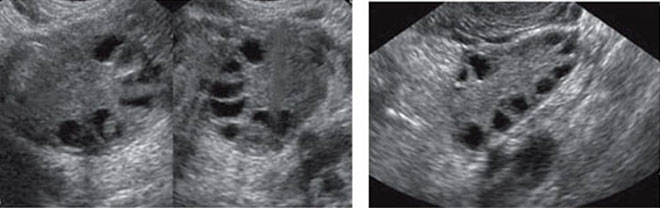

После выхода из фолликула яйцеклетка живет около 2-х дней, если в этот период оплодотворение не произошло она погибает. Желтое тело также разрушается, что становится толчком к началу менструации. До овуляции обычно определяются доминантные фолликулы (1-2) и несколько антральных. Но если их значительно больше (8-10), то УЗИ выявляет мультифолликулярные яичники.

Если при исследовании УЗИ обнаружены 8-10 фолликулов, это говорит о признаках мультифолликулярных яичников. Но в большинстве своем это считается вариантом нормы. Периодически с подобным может столкнуться каждая четвертая здоровая женщина. В норме в течении цикла развивается до 7 фолликулов. Развитие же большего количества фолликулов может произойти однократно или наблюдаться в течении каждого цикла